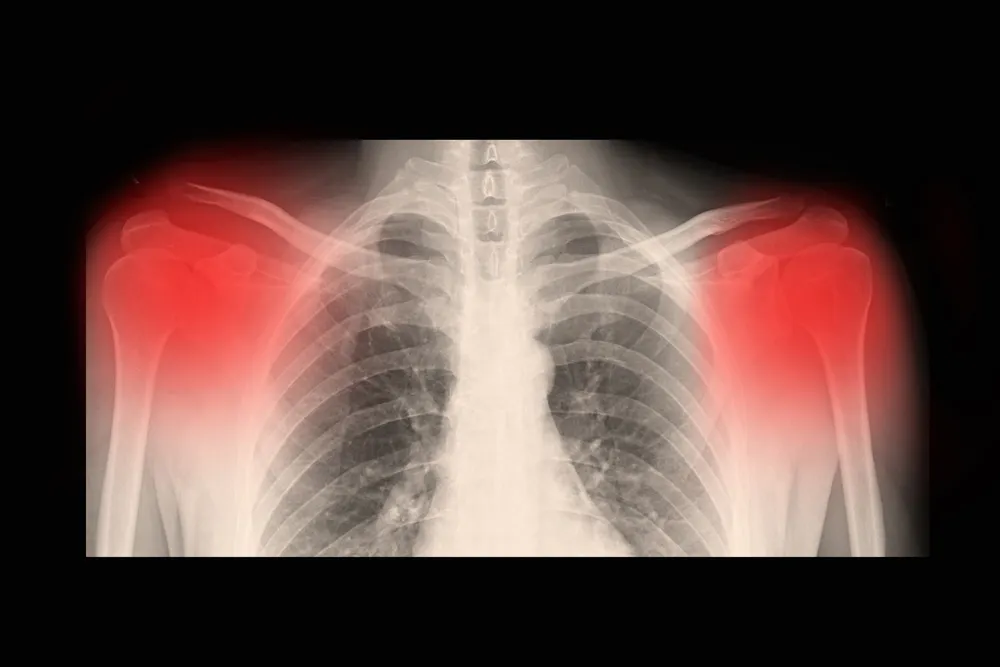

- Rayos X. Podemos observar si existe una fractura en el hueso y pequeñas manchas podrían ser indicadores de metástasis ósea.